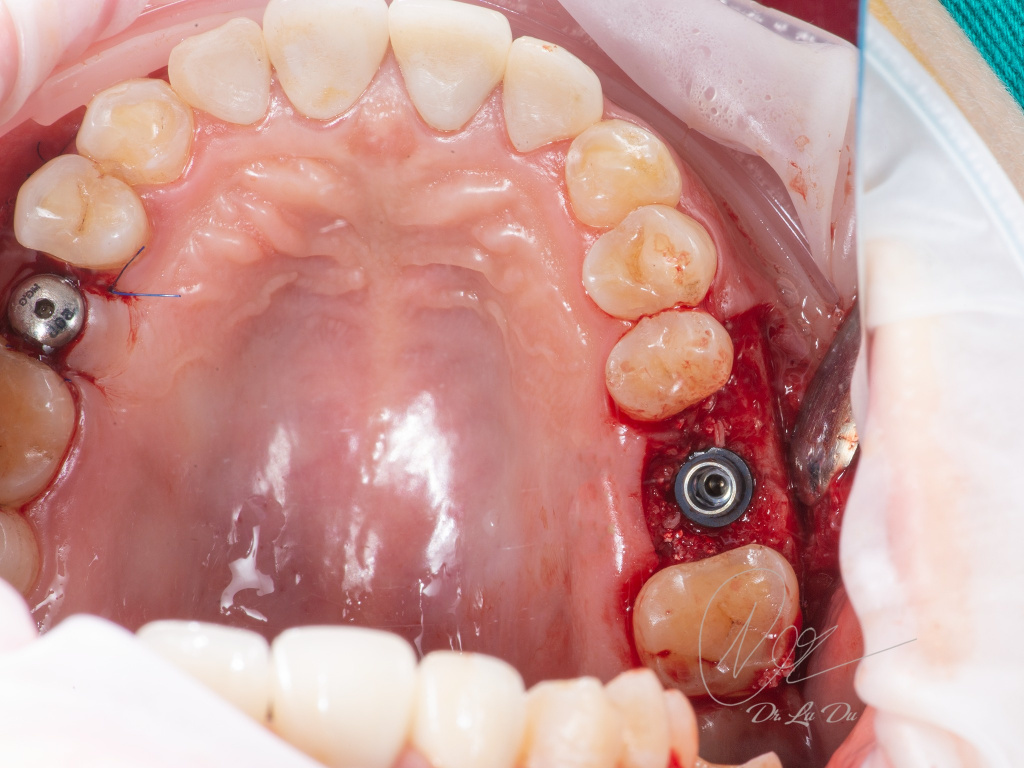

Имплантация AnyRidge с двусторонним закрытым синус-лифтингом.

Осложнения: правосторонний гайморит.

Кейс MINEC: Dr Lu Du